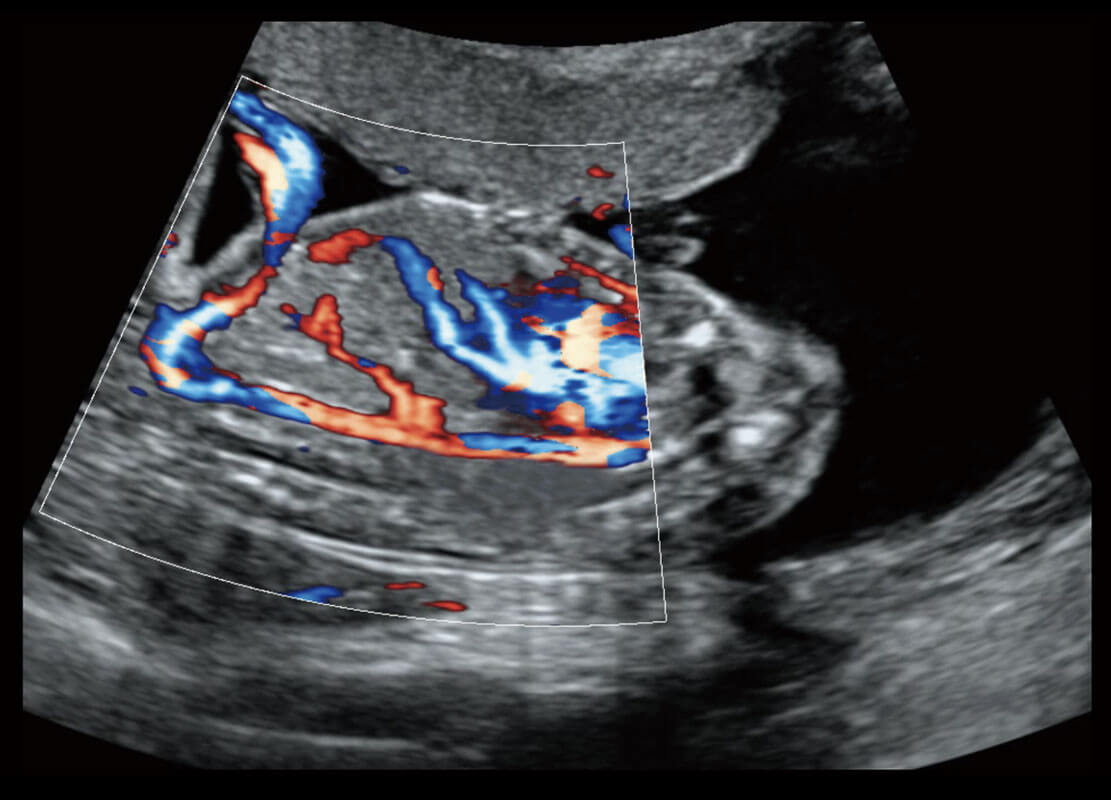

P60搭载一系列胎儿心脏成像技术,实现精细的胎儿心脏评估。

四腔心血流

右室双出口